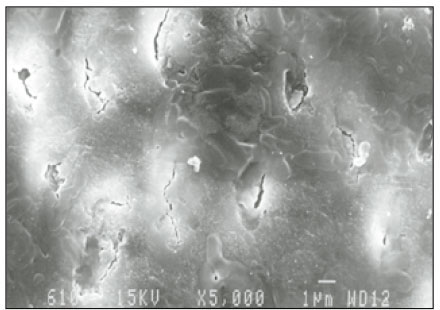

Fig. 1

Control group showing that most of the orifices of dentinal tubules were closed. ×5,000

In the controls and experimental groups brushed for 45 minute, a smear layer covered most of the surface of the specimens. Few dentinal tubule orifices were seen(Figs. 1 and 2).